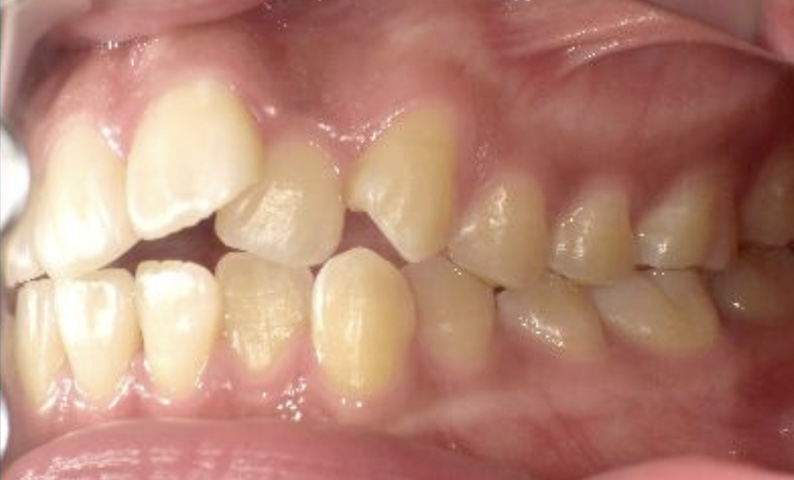

症例_023 上顎だけの部分矯正

治療期間:9ヶ月金額:30万円+税女性前歯のガタガタ上の前歯だけ

| Before | After |

|---|---|

|